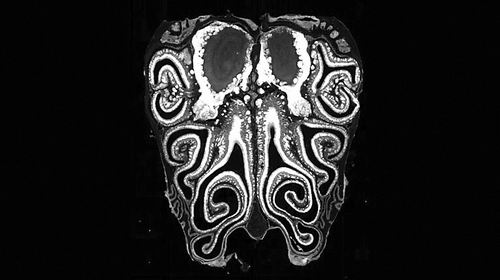

小鼠鼻腔的显微镜横截面图像,显示了鼻腔上皮的解剖结构。图片来源:Datta Lab

在研究中,科学家对来自数百只小鼠的约500万个神经元进行了检测。他们首先通过单细胞测序确定了由鼻腔神经元表达的嗅觉受体,然后利用空间转录组学绘制了关键基因的表达位置图谱。研究人员由此确定了这些受体的位置,并证明它们总是以从鼻腔顶部延伸至底部的水平条纹形式排列。

“每个受体在鼻腔中都占据一个特定的位置。鼻腔中有上千个位置,每个受体基本上都会在一个条带中表达,而这些受体条纹会与其他条纹发生重叠,最终形成上千个相互交错的条纹。”论文共同作者、美国哈佛医学院的Sandeep Robert Datta说。